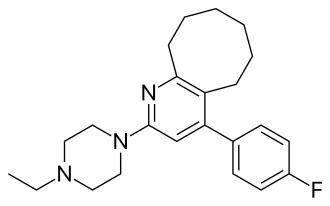

| Formula | C23H30FN3 |

| Molar mass | 367.512 g·mol−1 |

| 3D model (JSmol) | |

| |

Blonanserin has a relatively high affinity towards the 5-HT6 receptor perhaps underpinning its recently unveiled efficacy in treating the cognitive symptoms of schizophrenia.[7] The efficacy of blonanserin can in part be attributed to its chemical structure, which is unique from those of other atypical antipsychotics.[10] Specifically, the addition of hydroxyl groups to blonanserin's unique eight membered ring results in the (R) stereoisomer of the compound demonstrating increased affinity for the indicated targets.[11]